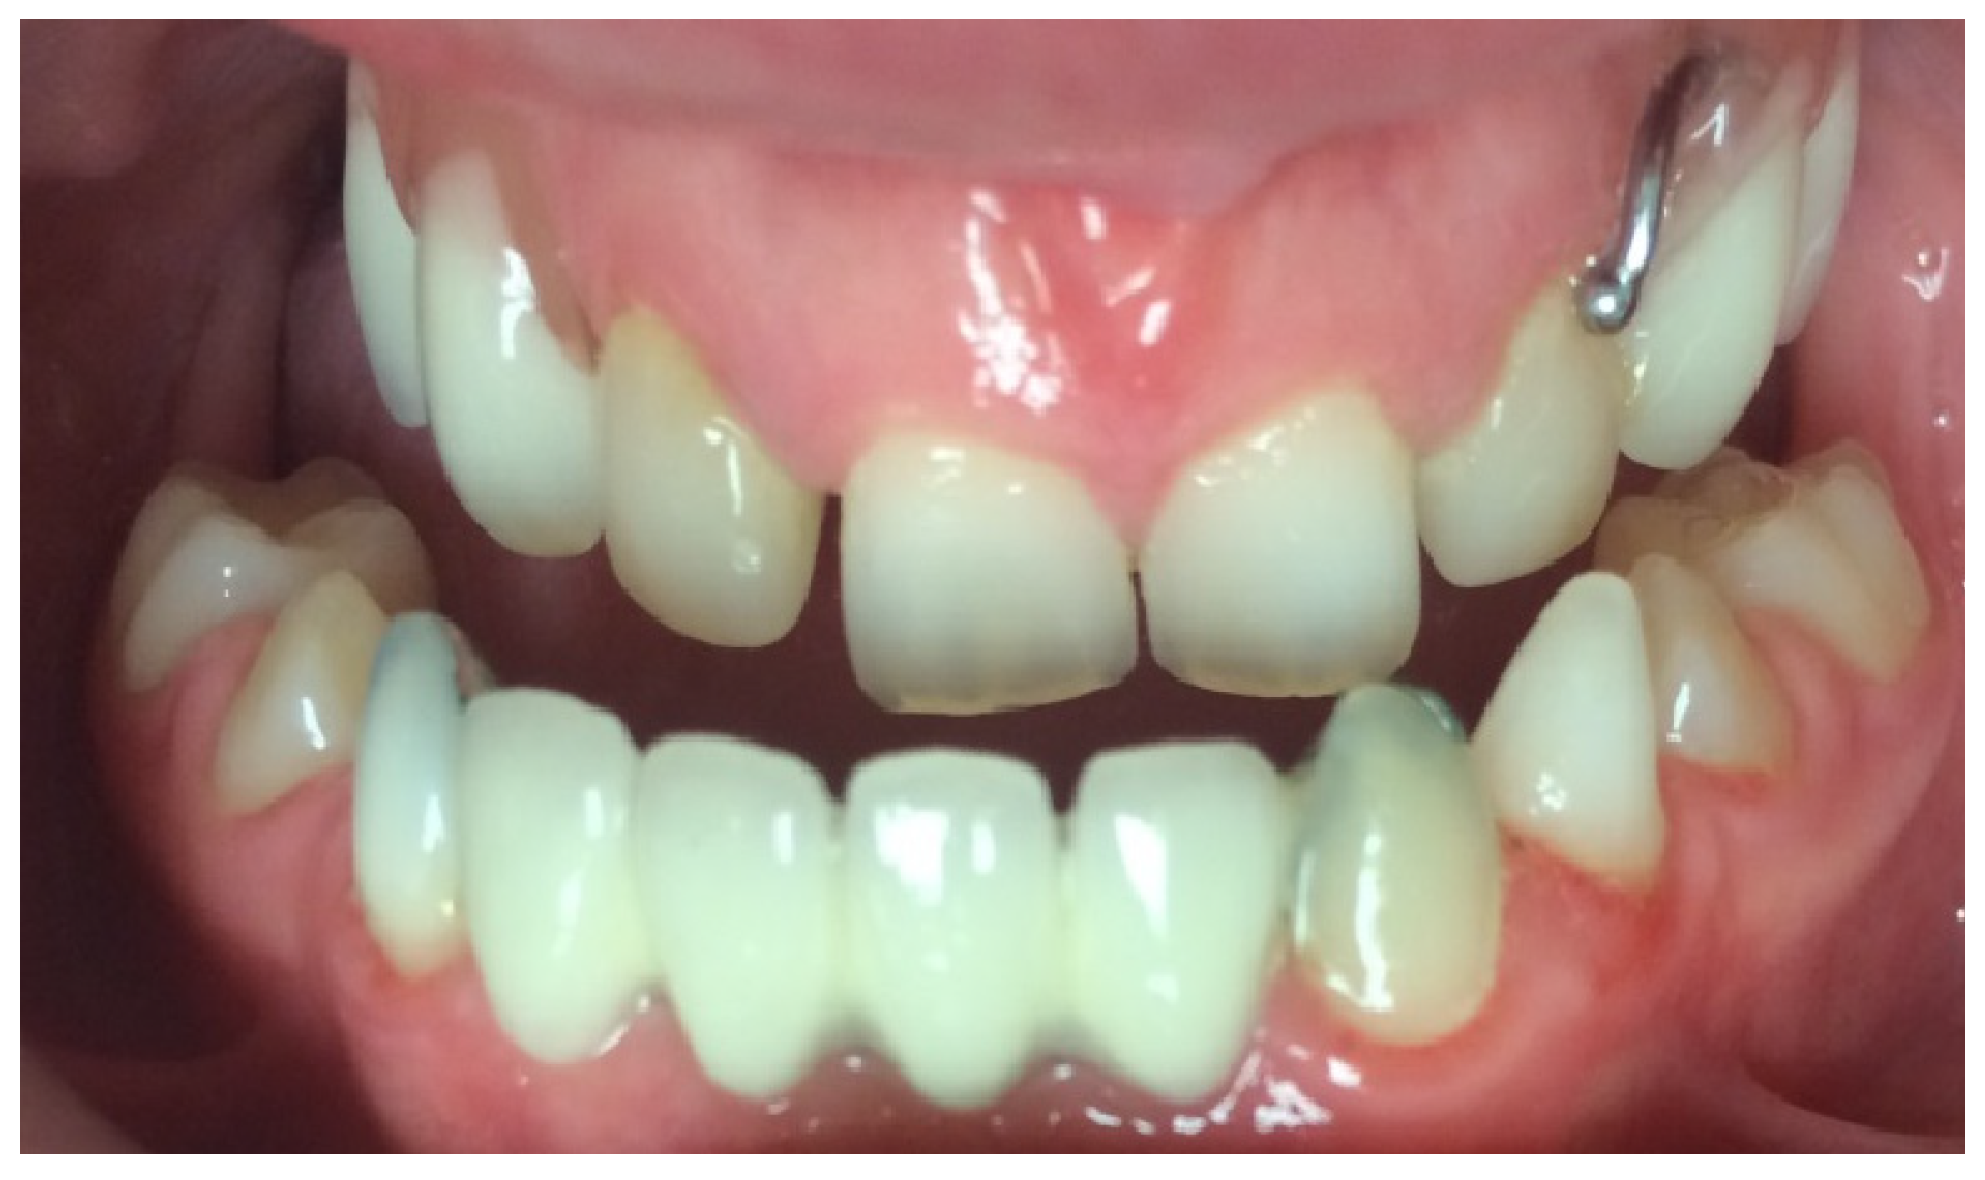

At the initial visit, the permanent teeth present were 15, 34, 33, and 44. The primary teeth present were 75, 72, 81, 82, and 85. Several dental anomalies were observed: The mandibular primary canines (73 and 83) were conical in shape, the maxillary right lateral incisor (12) was peg-shaped, and microdontia was noted in the maxillary central and lateral incisors (11, 21, and 22). Erosive wear was also evident on the maxillary primary molars and canines (54, 53, 63, and 64), suggesting the structural weakening of enamel (Figure 1, Figure 2 and Figure 3).

The child exhibited a narrow maxillary arch along with skeletal class III, resulting in a complete lack of occlusal contact, along with a reduction in both overjet and overbite by approximately 2 mm. A midline assessment was not feasible due to the extent of dental anomalies. Reduced alveolar bone volume was observed to be associated with the underdevelopment of the alveolar ridge. The clinical findings were corroborated by a recent dental panoramic tomogram (DPT) provided by the referring dentist. Radiographic analysis confirmed the agenesis of nineteen permanent teeth, as well as the presence of an impacted mandibular right second premolar (tooth 45) (Figure 4).

Figure 1. Intra-oral photograph, frontal view.